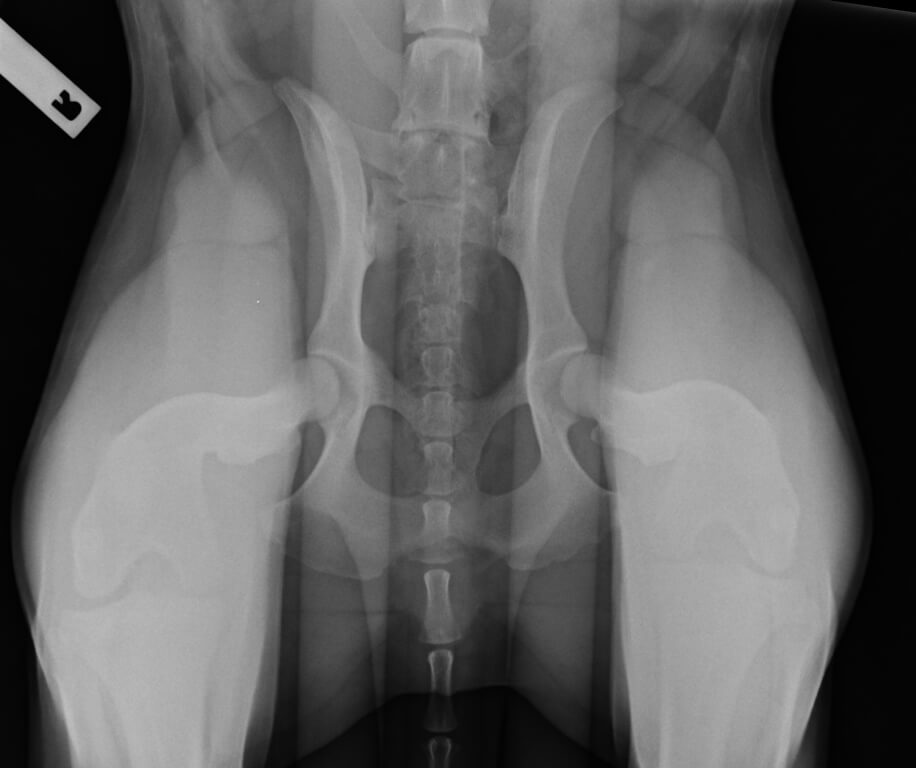

• PennHip Hip Dysplasia Screening

PennHip